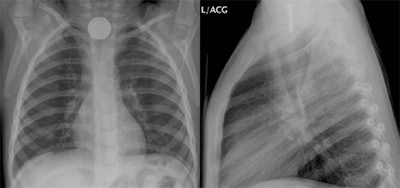

In any cases of clinical suspicion, a simple two-view chest/neck x-ray should be obtained to diagnose and distinguish a button battery with the “double ring” sign from the ingestion of a simple coin. (See Figure 1.)